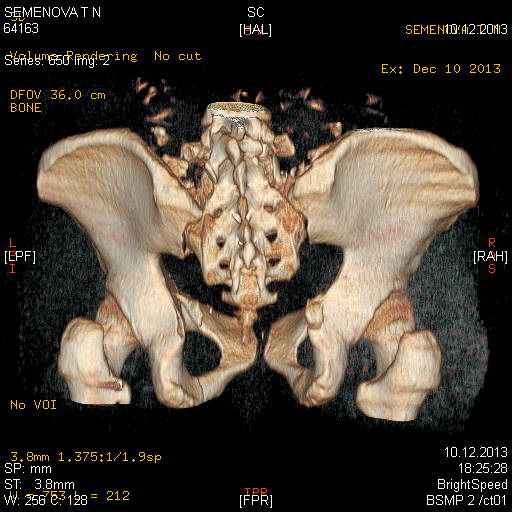

Доброго времени суток коллеги! Прошу вас, подсказать тактику в решении

оперативного лечения следующего сложного повреждения таза. Был ли опыт в

фиксации подобных повреждений?

Травма 03.12.2013,больная переведена из лечебного учреждения соседней

области. На данный момент у больной следующий диагноз: ЗЧМТ,сотрясение

головного мозга;Закр. травма грудной клетки,множественные переломы ребер

справа с повреждением ткани легкого, правосторонний гемопневмоторакс,

состояние после торакоцентеза; Закр.травма живота,разрыв

селезенки,гемоперионеум, состояние после лапаротомиии спленэктомии;

Закр. оскольчатый перелом сред-верх\3 левой бедренной кости, состояние

после накостного металлостеосинтеза; Закр.поперечный переломовывих на

уровне S1S2, многооскольчатый перелом латеральных масс крестца с обеих

сторон,перелом обеих лонных и седалищных костей.

Перелом поперечных отростков L1,L2,L3,L4, L5 позвонка справа. ШОК 3ст.

Вкратце изложил диагноз.

В настоящее время состояние больной тяжелое. Первым этапом планируем

наложить АНФ (переднюю раму) После стабилизации состояния необходимо

будет выполнить фиксацию.

Имеется один вопрос - какие импланты необходимы т.е. в какой комбинации

и какая последовательность фиксации?